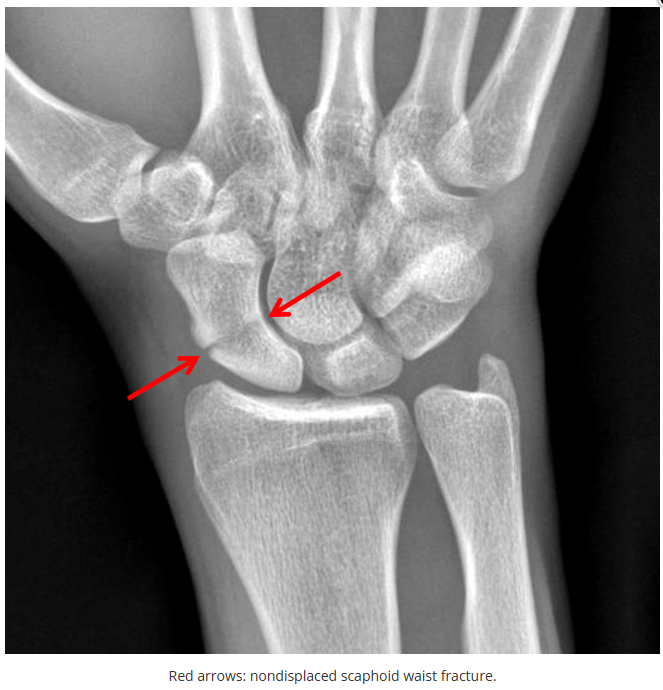

今天是腕部与手的X线片。所有X线片都

带有标注和说明

,可以选择长按图片,

自动翻译相关说明